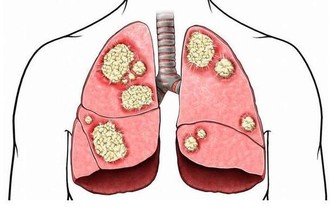

俗話說“傷在兒身,痛在娘心”,有時候孩子生病更令大人傷心,恨不得所有的痛苦由自己代替。今天要說的是白血病,聽到這個病相信很多人第一印象就是光著頭、戴著口罩的孩子,他們不能隨便外出,不能亂吃外面的餐飲,擔心交叉感染。看著孩子眼巴巴地望著窗外同齡小伙伴自由奔跑,大人心裡也不好受。

在兒童腫瘤數據中,超過一半的數據由白血病“貢獻”,而且還在以每年3-4萬的速度往上增加。在治療的同時我們也在深思,為什麼受傷的總是孩子?

孩子身體有效,但是細胞很活躍,代謝和更新的速度比成年人快,如果外界環境中存在不良因素,細胞在分裂的過程中就可能“出差錯”,最後形成癌細胞。